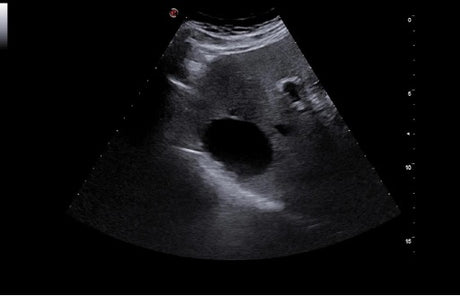

La qualité d’image est au cœur de la philosophie Esaote. Grâce à ses sondes de dernière génération et à son traitement du signal avancé, la marque permet une visualisation fine des structures anatomiques, même les plus profondes. Leurs échographes intègrent des écrans tactiles haute résolution, une interface claire et une connectivité complète, favorisant un flux de travail rapide et efficace.

Les échographes Esaote offrent une restitution d’image d’une grande précision, permettant un diagnostic fiable dans toutes les spécialités. Le traitement numérique optimise le contraste et la netteté, réduisant les artefacts et améliorant la détection des tissus pathologiques. Ces performances sont particulièrement appréciées en gynécologie, où la lisibilité des structures pelviennes ou obstétricales est déterminante.